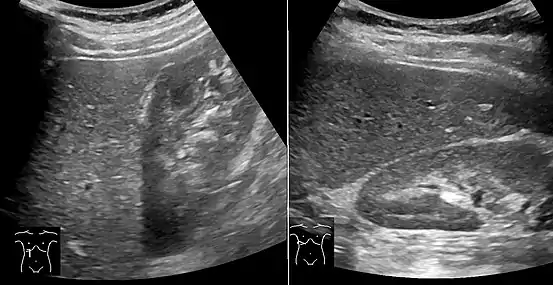

On abdominal ultrasonography, steatosis is seen as a hyperechoic liver as compared to the normal kidney.

Liver steatosis (fatty liver disease) as seen on MRI. Multiecho MR sequence in a healthy liver (top row) and a liver with severe steatosis (bottom row) are shown. In the healthy liver, the signal does not vary much in the different echoes. In the steatotic liver, the signal varies greatly between in and out phase echoes. Algebraic combination of these images can be used to accurately quantify liver steatosis. Abdominal ultrasonography with the liver and kidney side by side (left image) may give a false impression of hyperechogenic liver, so it's preferably done with the organ borders facing the ultrasound probe (right image, of the same case).

Abdominal ultrasonography with the liver and kidney side by side (left image) may give a false impression of hyperechogenic liver, so it's preferably done with the organ borders facing the ultrasound probe (right image, of the same case). Abdominal ultrasonography of focal steatosis. It is distinguished from a tumor by not compressing the hepatic vein.

Abdominal ultrasonography of focal steatosis. It is distinguished from a tumor by not compressing the hepatic vein.